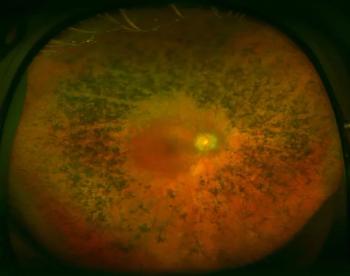

The study investigates 3-year intravitreal implant in eyes with active noninfectious posterior uveitis.